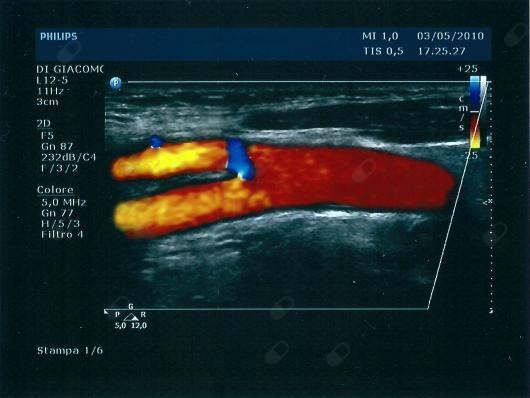

Mi sono laureato nel 1985 all'Università di Roma La Sapienza e lì mi sono specializzato in Chirurgia Generale. Ho avuto la fortuna di iniziare ad operare molto presto grazie ad uno dei miei tre maestri di chirurgia, Giacomo Scillamà, che mi ha insegnato i rudimenti del mestiere. Nel frattempo ho continuato a seguire le orme di Antonino Cavallaro, mio professore e relatore alla laurea e alla specializzazione, che mi ha permesso di coltivare una passione che avevo già preso da mio padre, cardiologo e angiologo: la chirurgia vascolare. Appena specializzato sono corso dal mio terzo maestro, John G. Pollock, che a Glasgow mi ha insegnato tutti i trucchi della chirurgia vascolare fornendomi, inoltre, un Full Training. Contemporaneamente a tutto ciò, ho continuato ad eseguire esami ultrasonografici, in particolare ecocolordoppler, e la scleroterapia dei capillari e delle vene. Attualmente sono consulente presso alcuni studi di Roma e provincia e pratico la chirurgia presso due strutture, la Nuova Itor (accreditata) e la Sanatrix (privata).

• Ecocolordoppler

200 €